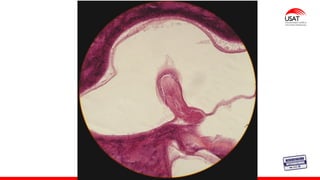

Membrana timpánica